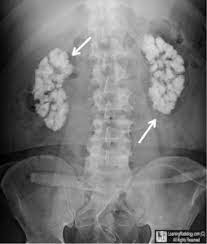

- Nephrocalcinosis:

- Which refers to renal parenchymal calcification:

- Is found in less than 5% of patients with PHPT and is more likely to lead to renal dysfunction

- In several studies, clinically silent kidney stones were reported in:

- 7% to 21% of patients with PHPT:

- Patients with undiagnosed (subclinical) nephrocalcinosis or calcium kidney stones are regarded as having symptomatic disease:

- Regardless of the absence of symptoms:

- Thus, these patients meet criteria for surgical intervention

- For patients who do not have other overt indications for surgery:

- Some UpToDate authors and editors obtain renal imaging (ultrasound, computed tomography [CT], or abdominal radiograph) to look for nephrocalcinosis or asymptomatic nephrolithiasis at the time of the original evaluation for PHPT:

- Ultrasound is typically the imaging modality used